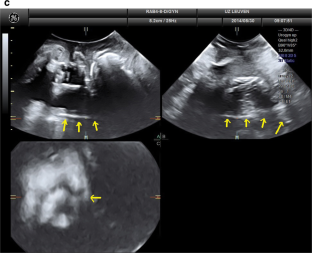

There were 17 women in the PP and 25 in the PVDF mesh group, without differences in baseline demographics. None had significant prolapse, recurrence, symptoms, or complications. On TPUS, mesh was visible in all patients both caudally (perineal) and cranially but was more echogenic in the PVDF mesh group. Mesh length from distal to proximal that was visible on TPUS was longer for PVDF mesh, for both anterior and posterior vaginal arms (all P < 0.05), and for mesh above the vaginal apex (P = 0.002). The inferior aspects of the mesh showed areas of double mesh layers, suggesting folding in 80% of women in both groups, without symptoms.

Fig. 1